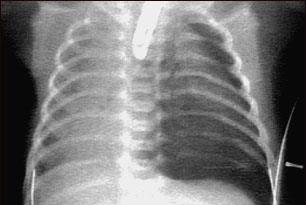

A collapsed lung, or pneumothorax, is the collection of air in the space around the lungs. This buildup of air puts pressure on the lung, so it cannot expand as much as it normally does when you take a breath.

A collapsed lung occurs when air escapes from the lung and fills up the space outside of the lung, inside the chest. It may be caused by a gunshot or knife wound to the chest, rib fracture, or certain medical procedures.

In some cases, a collapsed lung occurs without any cause. This is called a spontaneous pneumothorax. A small area in the lung that is filled with air (bleb) can break open, sending air into the space around the lung.

EXAMS AND TESTS

There are decreased or no breath sounds on the affected side when heard through a stethoscope. You may have low blood pressure.

Tests include: